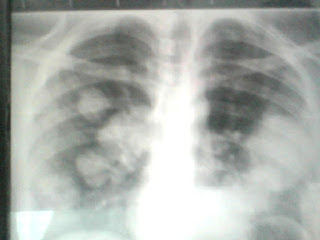

One year before the current presentation, he had noticed painful swelling of his right testis. He had consulted a doctor but didn’t follow the advice. An X-ray chest in ER taken is shown below suggestive of canon ball shadows.

Cannonball metastases:

Multiple well-defined lesions in both lungs are called cannonball metastases due to their large, round appearance. This pattern is the common manifestation of metastatic disease. The rich vascular bed of the lungs is hospitable to tumor emboli. In some patients, however, a history of primary cancer is lacking at initial presentation. Such a sole presentation of cannonball metastases is classically seen in germ cell tumor, choriocarcinoma, and endometrial cancer.